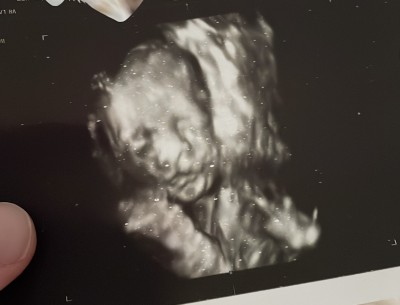

Detaylı ultrasona girdim perinatoloji baktı herleyi iyiydi çok şükür 23 haftalık bu arada bebek en sonunda yüzünü 3 boyutlu açtı resim vermek için aa dedi üst dudakta hafif çentik mi var diye şüphelendi ama esnerken görmüştüm siyah beyazda dedi. Başka doktoru çağırdı o göremedi sanki çentik ama ultrason resminde çıkmış aklım karıştı 😕

Gebelik haftası 23+4

Siyah beyaz ultrasonda sorun görmedi sanki 3 boyutluyy açınca bi şüphelendi

Salı günü bir daha bakacak perinatoloji hafif çentik den şüphelendi gelen ikinci doktor göremedim öyle bişey dedi ama resimde belli sanki